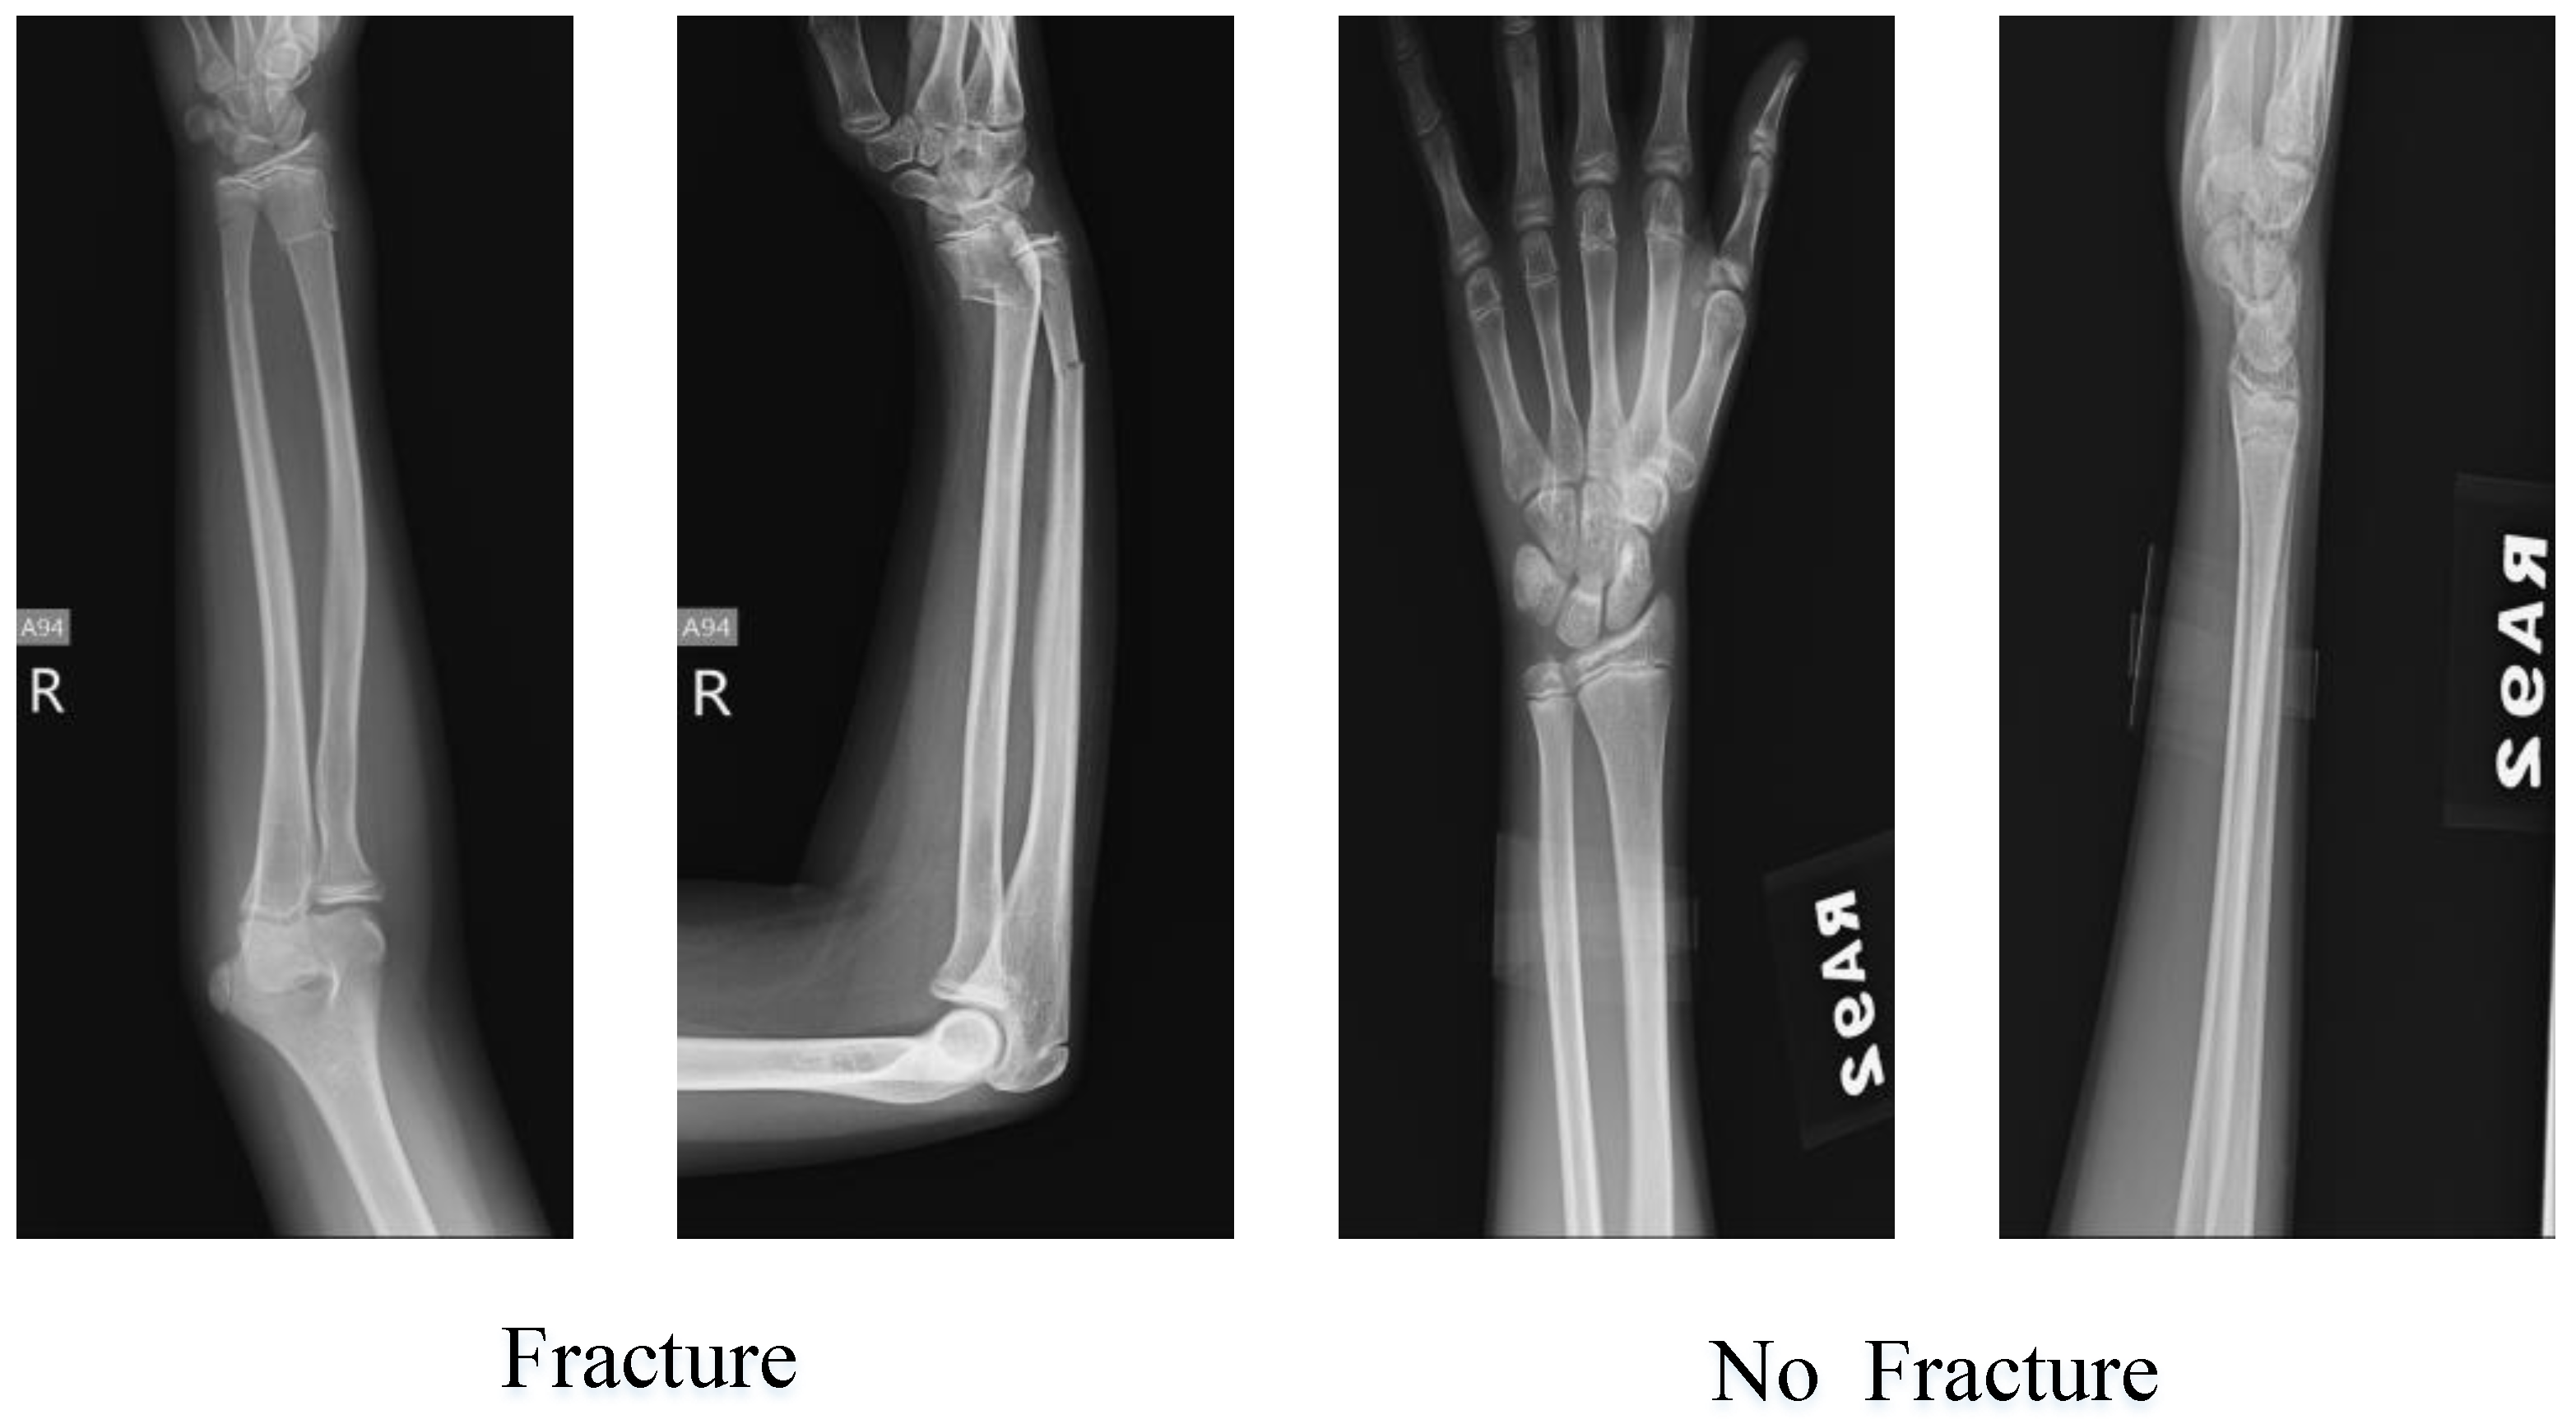

Testing the Proposed Pyramid Deep Feature Extraction Model with an Alternative Dataset

- Pediatric Radius Fracture. Available online: https://www.kaggle.com/datasets/khhsu3/pediatric-radius-fracture?select=%E9%81%A0%E7%AB%AF%E6%89%8B%E8%85%95%E6%9C%89%E9%AA%A8%E6%8A%98 (accessed on 18 October 2023).